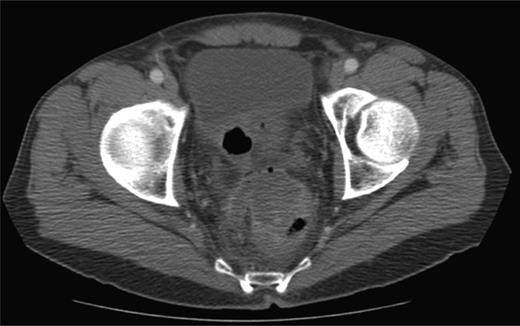

In the 6-week follow-up, repeat CT demonstrated eccentric thickening of the rectosigmoid with interval development of an adjacent complex pelvic fluid collection with supralevator extension measuring 3.5 × 2.5 cm (Fig. 2a and b). Percutaneous needle biopsy revealed pus, and a drainage catheter was left in place (Fig. 3a and b). The patient did not improve, was reimaged and was found to have collection extending into the ischiorectal fossa and supralevator space (Fig. 4). Owing to refractory pain and persistent leukocytosis, the patient was taken to the operating room for examination under anesthesia. No fistulous tract or internal drainage was noted within the rectal vault; however, consistent with the imaging, external induration was observed along the right ischiorectal fossa, where, upon incision, a large purulent cavity was evacuated. On evening rounds, the patient was noted to have a marked leukocytosis and frank stool coming from the ischial wound, and he was taken emergently to the operating room for diagnostic laparotomy where a perforated diverticulum adherent to the pelvic sidewall was identified (Fig. 5). Therefore, a Hartmann procedure, drainage of supralevator abscess, irrigation and debridement of the right ischiorectal wound, was performed.

CT scan demonstrating ischiorectal extension of oral contrast and air tracking.